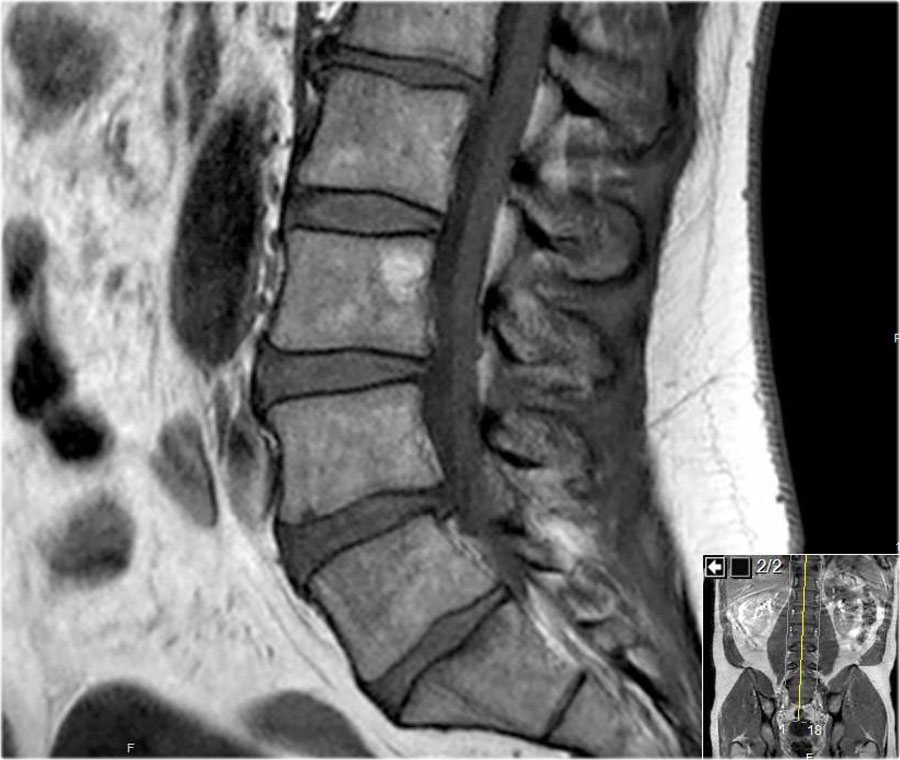

Các hình ảnh cắt dọc chuỗi xung T1W cung cấp nhiều thông tin chẩn đoán nhất.

Trước khi bắt đầu tìm kiếm bất kỳ thoát vị nào, hãy quan sát kỹ các mô trước cột sống và tủy xương.

Khi đã phát hiện bất thường, hãy đối chiếu các phát hiện này với hình ảnh chuỗi xung T2W (hình).

Trước tiên hãy cuộn qua các hình ảnh chuỗi xung T1W mặt phẳng đứng dọc này.

Các dấu hiệu là gì?